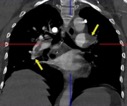

В статье представлен случай успешного хирургического лечения тромбоэмболии легочной артерии у пациентки с высоким риском ранней сердечной смерти на фоне парадоксальной эмболии, осложненной острым нарушением мозгового кровообращения. Криптогенное острое нарушение мозгового кровообращения в комбинации с тяжелой прогрессирующей правожелудочковой недостаточностью на фоне ТЭЛА обусловливает серьезные трудности при принятии решения в отношении тактики лечения у данных больных. Внутрисердечная локализация тромбоэмбола, угрожаемая развитием не только рецидива тромбоэмболии легочной артерии, но и парадоксальной эмболии требует незамедлительного выполнения комплекса дифференциально-диагностического обследования, направленного на верификацию патофизиологического механизма развития заболевания, что во многом определяет эффективность проводимого лечения. Анализ доступных литературных данных, приведенный в работе, а также анализ клинического случая позволяют выработать тактический алгоритм в этой группе пациентов и определить показания к открытому оперативному вмешательству.